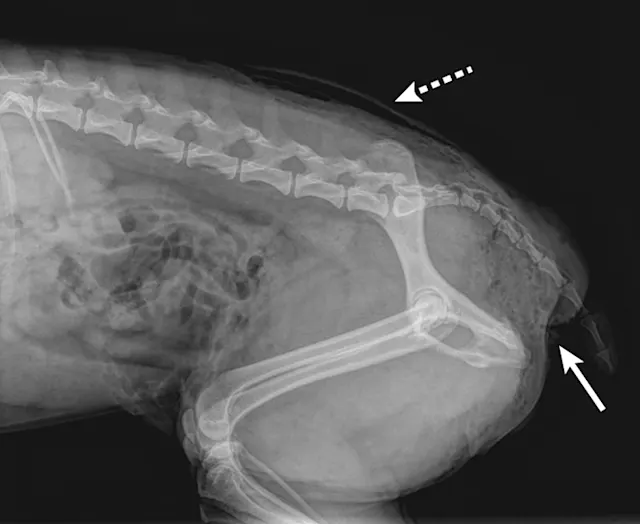

FIGURE 1

Perineal subcutaneous emphysema (solid arrow). Bites near the tail should be inspected for nerve injury and rectoanal damage. Subcutaneous emphysema can also be seen in the dorsocaudal area (dashed arrow).